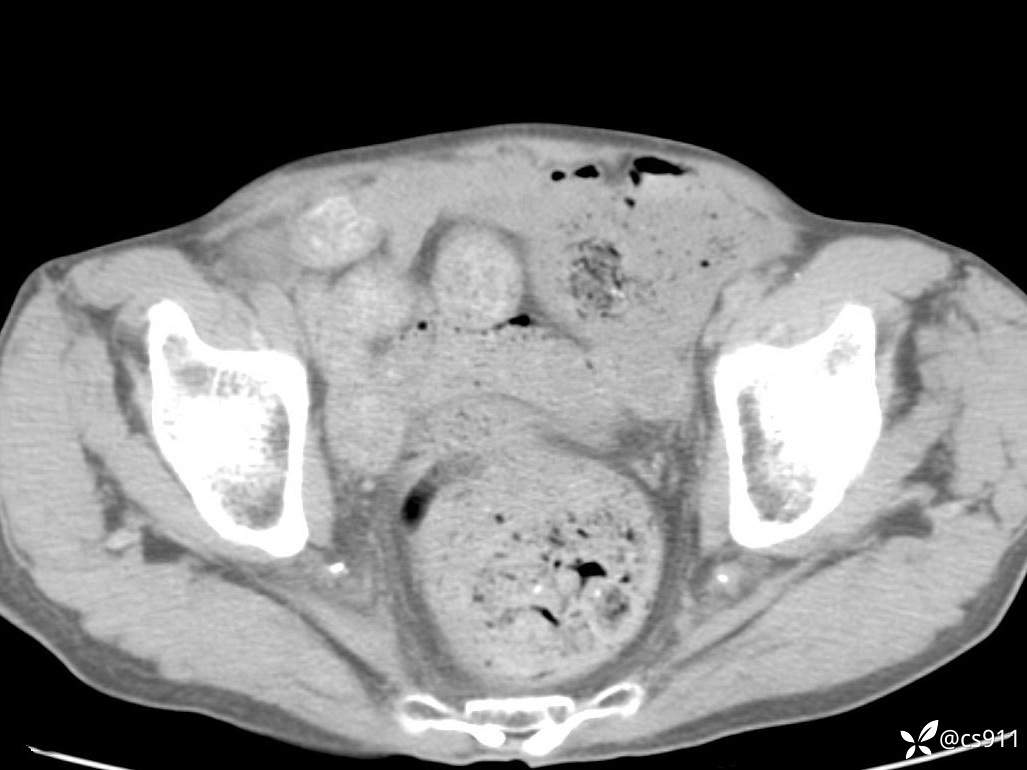

急腹症之急诊CT,原因?答案公布

男,77岁,腹痛、腹胀伴恶心呕吐1天。呕吐胃内容物,非喷射性呕吐,有咖啡色样胃内容物,诉有胃穿孔病史。查体:全腹平,下腹部压痛,全腹无反跳痛,叩诊呈浊音,移动性浊音阴性,肠鸣音减弱,1-2次/分。肛检:直肠未扪及明显肿物,可触及大量粪块。

T 36.6℃ P 80次/分 R 26次/分 BP 100/60mmHg

白细胞(WBC) H 14.55 10e9/L 4-10

红细胞(RBC) 4.58 10e12/L 4.3-5.8

中性粒细胞百分率(NEUT%) H 85.7 % 40-75

血淀粉酶(AMY) HH 1859 U/L 35-135

癌胚抗原(CEA) H 27.44 ng/ml 0-5

呕吐物 潜血试验 * 阳性 阴性

患者轮椅入室检查神志清楚, 能配合摆位和呼吸